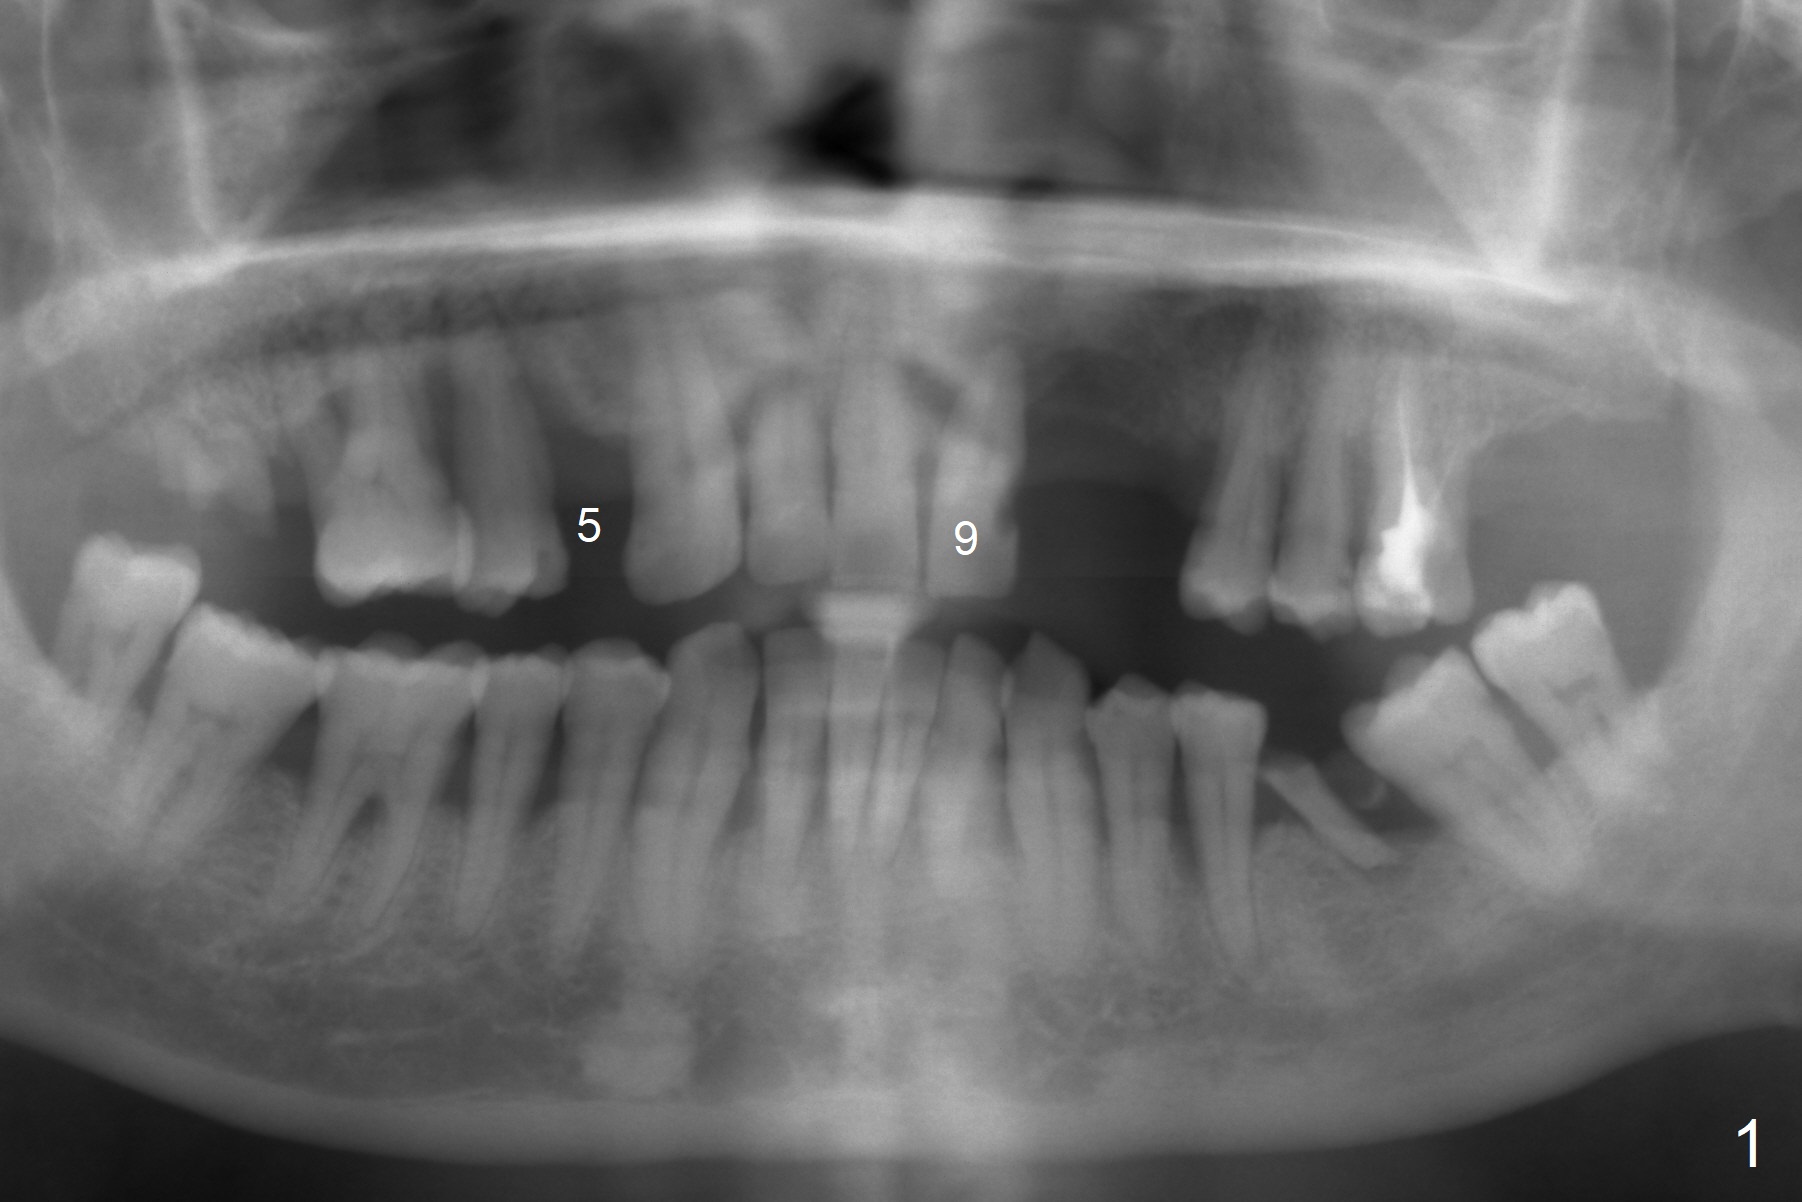

A 45-year-old man requests implant replacement for #5, 9 and 24-26 (Fig.1) after extraction of the tooth #9 (Fig.2). The teeth #24-26 have severe bone loss with mobility III (Fig.3). Since their roots are close to each other (Fig.4 (after extraction)), osteotomy will be initiated at #24 and 26 (Fig.5).